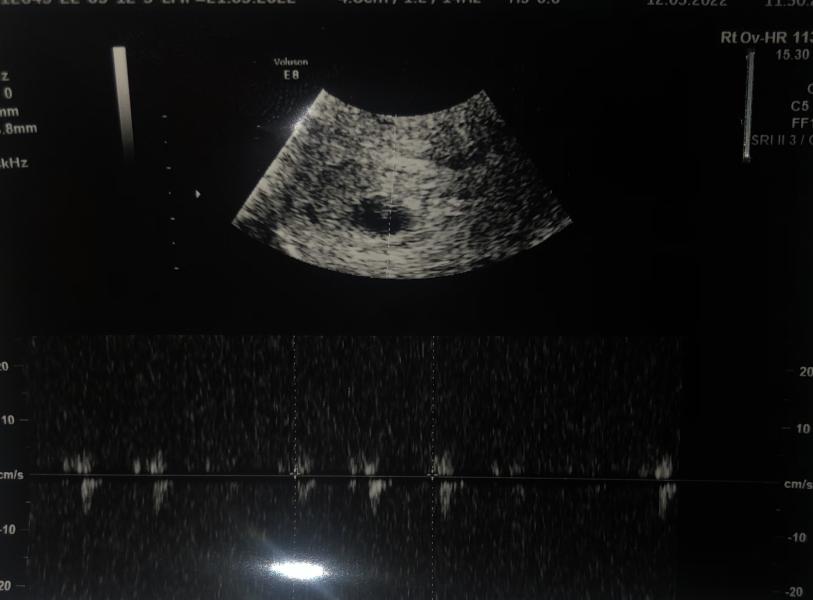

Девочки, на снимке внизу это значит что есть сердцебиение? Что-то на узи я не услышала сердцебиение и не дали послушать ,но написали 113 уд и вот такой вот снимок

От зачатия 4 недели и 4 дня, узист говорит прийти через 10 дней ,так и не услышала конкретного ответа,но хочется узнать нормально ли всё

Потому что на раннем сроке его не прослушать ,но оно присутствует

Если срок 4 недели всего, то наврятли ещё сердечко слышно.

Если написали сердцебиение, значит срок больше)